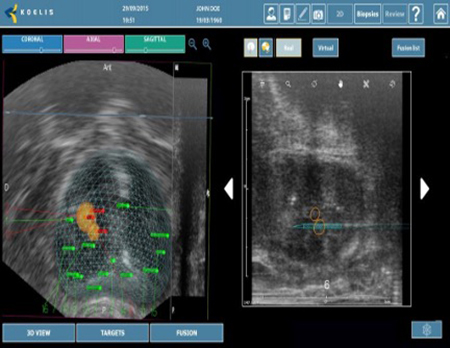

Koelis Trinity Perine

Υπερσύγχρονη πλατφόρμα πλοήγησης που επιτρέπει:

- Την ελαστική συγχώνευση τρισδιάστατων εικόνων Υπερηχογραφήματος και Μαγνητικής Τομογραφίας σε πραγματικό χρόνο μέσω του λειτουργικού συστήματος εντοπισμού Organ-Based Tracking Fusion( OBT Fusion).

- Aπεικόνιση του προστάτη σε τρισδιάστατη μορφή.

- Λήψη βιοψίας σε εικονικό και πραγματικό χρόνο

- Αναλυτική χαρτογράφηση της βιοψίας προστάτη.

- Δυνατότητα ανάκλησης των στοιχείων της βιοψίας για περαιτέρω μελέτη (follow up)

Ακολουθούν Εικόνες

TRINITY PERINE

OBT FUSION

OBT FUSION